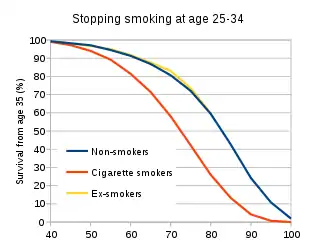

Smoking cessation is one the most effective methods for managing numerous smoke-related diseases and other immune diseases such as AIDs.[25][26] It brings both short term and long term benefits as the mucus clearance is improved in 48 hours and the mortality risk of lung cancer is halved in 10 years.[25] In addition, the immune system starts to recover in 15 days as the inhibitory effects of cigarettes on macrophages are removed.[27] The risks of morbidity and mortality of infectious diseases are significantly reduced in 1 year and become comparable with non-smokers after 5 years of quitting.[20] Meanwhile, the life expectancy after smoking cessation increased by 10 years with the reduced risks of these diseases.[28] Furthermore, early cessation in the age of 25-34 enhances the survival rate at the age of 35 by 20-30% compared with an average smoker.[29]